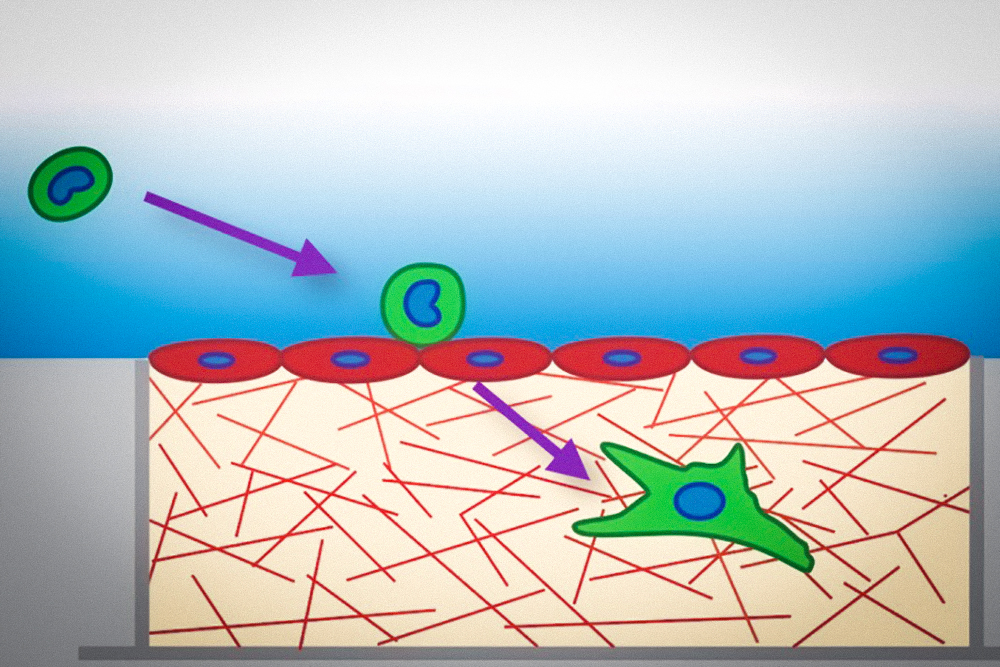

Иллюстрации из Cell Discovery: Удивительный мир науки через фотографии

Раздел: Фотоэссе